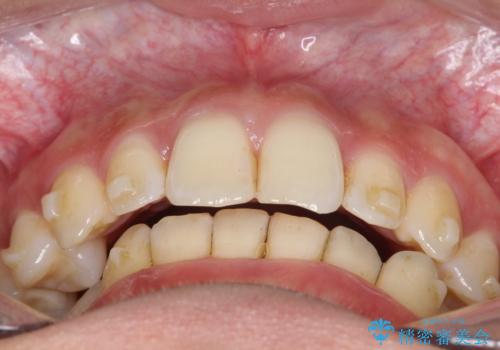

ディープバイト改善のためのインビザライン治療

- 患者様は、全体的な歯列のガタガタとディープバイト(深い噛み合わせ)を主訴として来院されました。診断の結果、ディープバイトを改善するためには、歯列全体の拡大が必要であると判断しました。治療には、透明なマウスピース型矯正装置「インビザライン」を使用し、歯を適切に拡大しながら歯並びを整える計画を立てました。治療期間はおおよそ2年を見込んで進め、最終的に見た目にも大きく変化をもたらすことを目指しました。

ディープバイトの治療には、奥歯の高さや前歯の位置に対する繊細な調整が必要です。本症例では、インビザラインによる歯列拡大を行うことで、噛み合わせを改善し、歯並び全体を整えました。治療過程では、歯間のスペースを確保するため、IPR(インタープロキシマルリダクション)を適宜行い、無理なく歯列の調整を行いました。治療後は、歯並びが大きく改善され、患者様の見た目にも大きな変化が現れました。インビザラインは透明で目立たず、治療中の見た目を気にされる患者様にも配慮した治療法です。